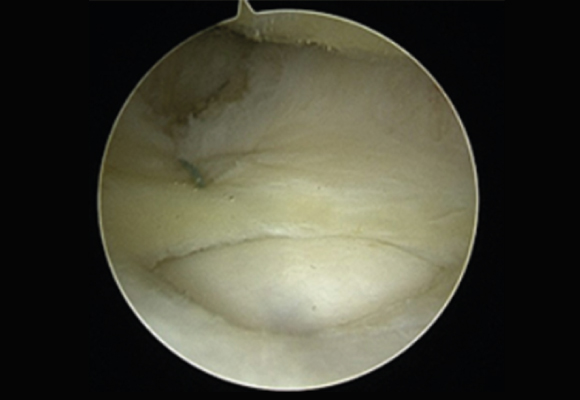

낭종 크기가 크고 통증이 심한 경우 무릎 뒤쪽의 혹을 제거하는 수술 시행

ㆍ환자 동의를 받은 자료이며, 이미지 사진은 실물과 다를 수 있습니다. (20.12.03)